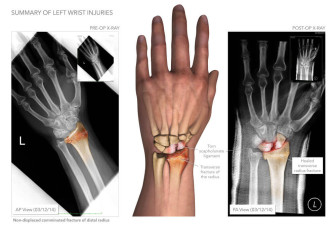

• Injury Summary